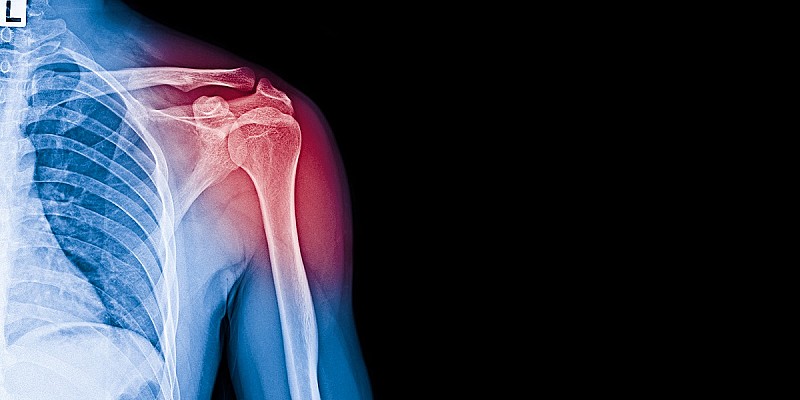

dolore tendini spalla

I risultati di un recente studio hanno dimostrato che il miglioramento della qualità della dieta può ridurre in maniera significativa il dolore muscoloscheletrico cronico, indipendentemente dalla perdita di peso.